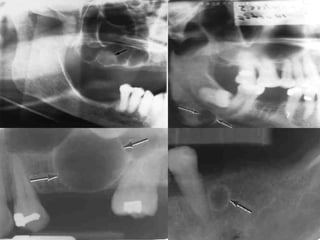

Radiographic features

 This cyst is evidenced in the

radiograph by widening of the

pericoronal space that

 reached 2.5 mm in width It

appears as radiolucent area

associated

with the crown of the un-erupted

tooth. This radiolucency may

be unilocular or multilocular in

appearance. If multicysts are

recognized, care should be

taken to rule out the possible

occurrence of odontogenic

cyst basal cell nevus bifid rib

syndrome.

 Radiographic features:

 Small well circumscribed radiolucent

area with definite border and surrounded

by a thin layer of sclerotic bone at the

apical or lateral surface of the root,

usually less than 1 cm in diameter.